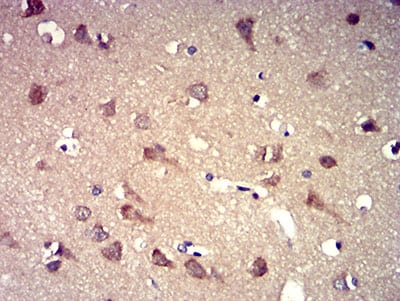

Immunohistochemical analysis of paraffin-embedded human cervical cancer tissues using P2RY8 mouse mAb with DAB staining.

Immunohistochemical analysis of paraffin-embedded human brain tissues using P2RY8 mouse mAb with DAB staining.